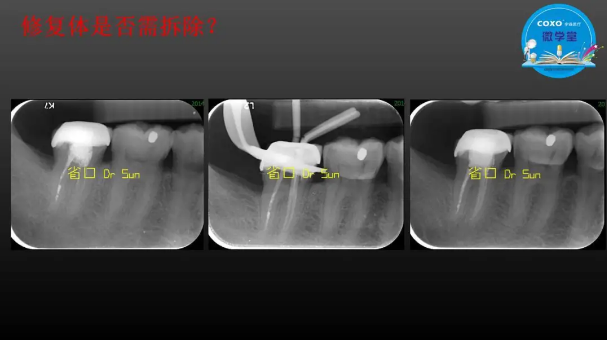

主講:孫書昱

主任醫(yī)師,牙體牙髓副主任, 廣東省口腔醫(yī)院牙體牙髓科 主任醫(yī)師。2003年碩士研究生畢業(yè),研究方向為牙體牙髓病學,擅長于牙體牙髓病的診斷、齲齒、牙髓炎、根尖周病的治療以及前牙美容修復。